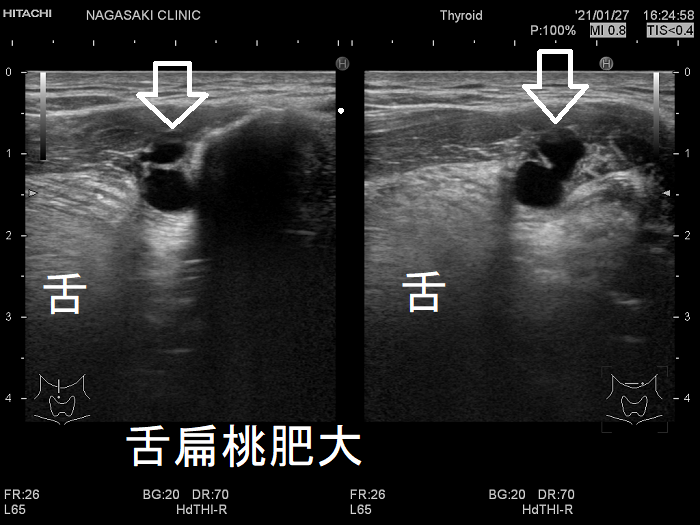

舌扁桃

舌扁桃は免疫を司るリンパ組織です。

1. 鼻・副鼻腔・歯・歯肉などの慢性炎症

2. 入れ歯の機械的刺激

により舌扁桃肥大や舌扁桃膿瘍に進展すると、喉(のど)の違和感が生じ、甲状腺の病気と勘違いすることがあります(甲状腺よりも遥か上なので鑑別は容易ですが)。また、舌扁桃肥大で閉塞性睡眠時無呼吸症候群(OSAS)を来す事もあります。

舌扁桃肥大 超音波(エコー)画像